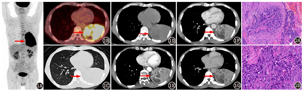

患者男,58岁,10余天前无明显诱因出现咳嗽,于外院治疗未见明显好转,1 d前出现高热来本院就诊。既往饮酒、吸烟30年。实验室检查(括号内为正常参考值范围):WBC计数19.77(3.50~9.50)×109/L,嗜中性粒细胞百分比89.30%(40.00%~75.00%),PLT 365(125~350)×109/L,C反应蛋白149.06(0~6.00) mg/L,降钙素原620(0~50) ng/L;肿瘤标志物神经元特异性烯醇化酶[1.76(0~1.63)×103 ng/L]、细胞角蛋白19片段[7.42(0~3.30)×103 ng/L]增高。多次痰涂片检查未发现肿瘤细胞和结核杆菌。行18F-FDG PET/CT及胸部CT(平扫+增强)(图1),综合考虑为左肺下叶肺癌伴纵隔及左肺门淋巴结转移。支气管镜检查示左主支气管末段"菜花"样新生物生长、左下叶支气管堵塞。左主支气管末段新生物活组织检查考虑为绒毛膜癌(图2)。后补充检测人绒毛膜促性腺激素(human chorionic gonadotrophin, HCG)18 267(0~2.6) U/L。全身其他部位未发现原发灶。男性肺原发性绒毛膜癌临床罕见,既往个案报道仅见于CT检查[1,2]。18F-FDG PET/CT作为无创性多功能影像检查方法,在评估患者全身累及情况时具有明显优势,但其代谢参数对该病的诊断价值尚待研究。